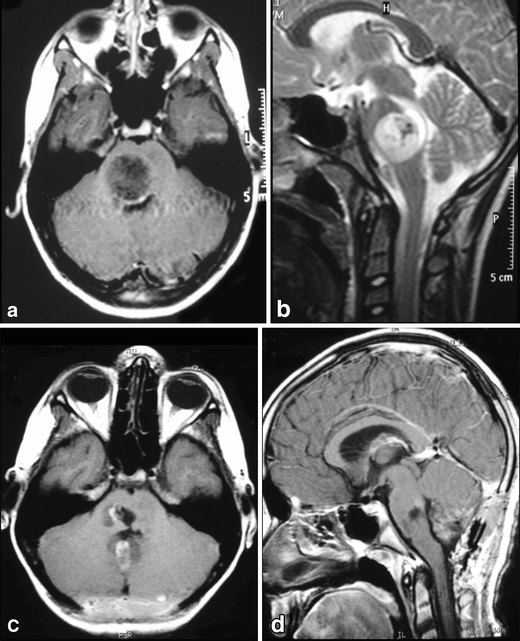

Fig. 7

figure 7

a, b A solid cystic tumor at the central portion of the midbrain with gadolinium enhancement growing towards the pineal region was removed by a central infratentorial supracerebellar approach. c, d 10-year follow-up shows no evidence of the lesion, which was a pilocytic astrocytoma